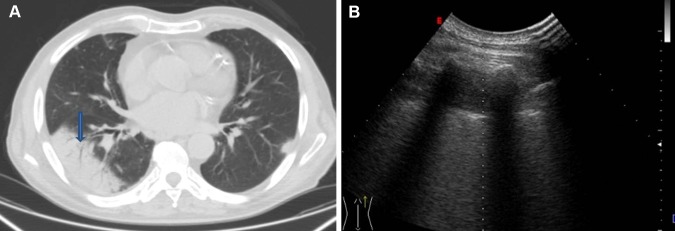

We also agree with the authors not paying emphasis on the results concerning “linear/arborescent bronchograms” [1]. Indeed, it should be stressed that no study or meta-analysis has so far demonstrated that such hyperechoic images specifically correspond to the CT imaging finding of the air bronchogram. Additionally, the CT detection of the air bronchogram is not associated with the US visualization in any case (Fig. 1). Finally, we have shown that such images can also be detected in lung neoplasm masses and are, therefore, not specific for pneumonia [5].

Fig. 1.

a CT scan showing subpleural pneumonia with air bronchogram (blue arrow) and b corresponding ultrasound image showing hypoechoic subpleural lesion in the absence of hyperechogenic spots or streaks from an air bronchogram